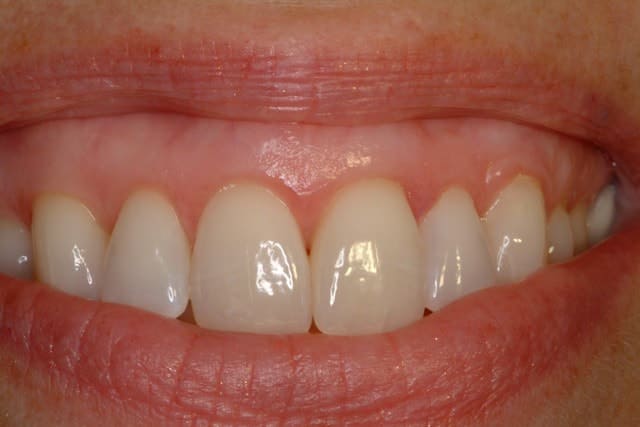

After

Before